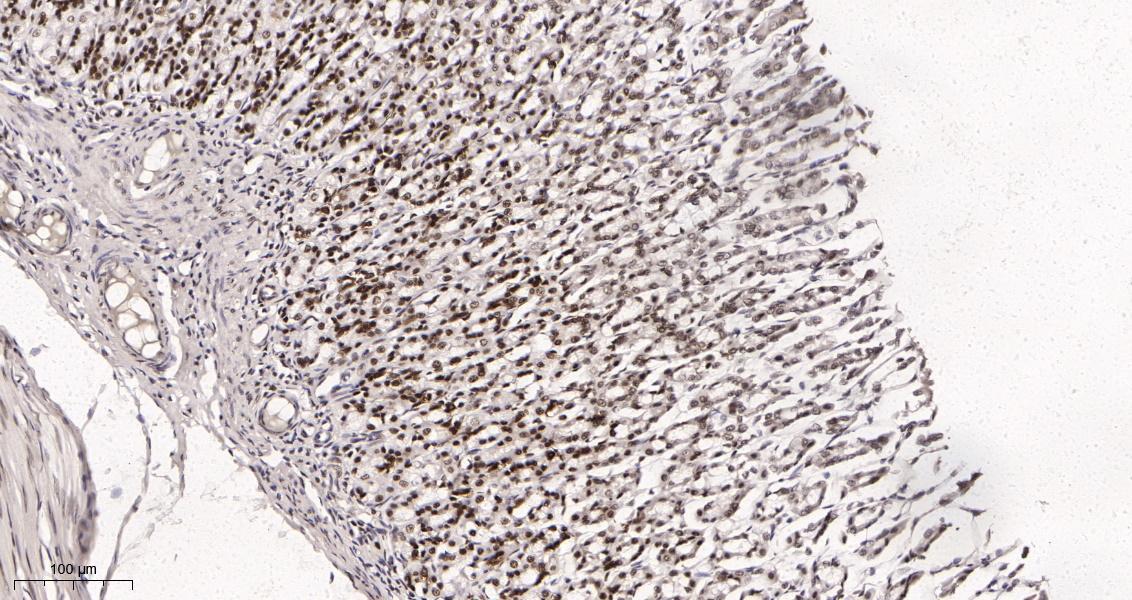

产品名称Rad21 (16H8) Rabbit Monoclonal Antibody

推荐应用WB,IHC-P,IF-P,IF-F,IF-ICC,IP,ELISA

稀释度IHC-P 1:200-1000,WB 1:1000-5000,IF-P/IF-F/IF-ICC 1:200-1000,ELISA 1:5000-20000,IP 1:50-200